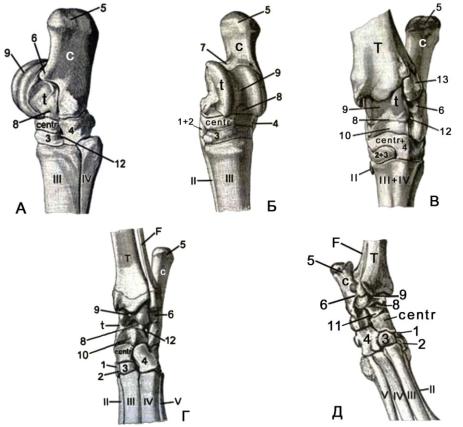

Анатомия: Блоки и сесамовидные кости в деталях